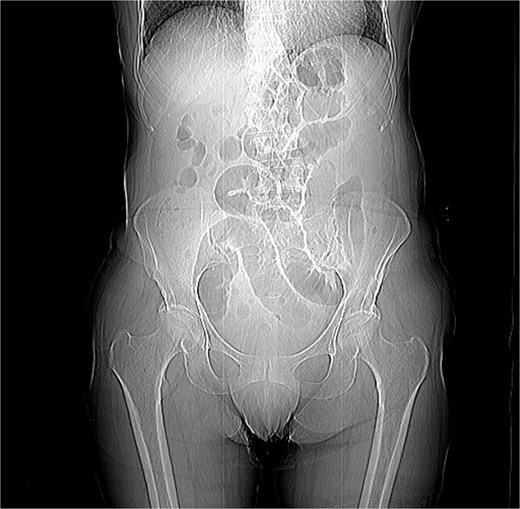

A 76-year-old female patient presented to the emergency department with abdominal pain and vomiting. A standard radiography (Fig. 1) and a contrast-enhanced abdominal CT scan revealed an intestinal obstruction caused by intussusception of the terminal ileum into the cecum (Figs 2 and 3). Laboratory tests showed elevated C-reactive protein levels and leukocytosis. Her medical history was significant for bilateral carotid artery stenosis (under treatment with clopidogrel), mild obstructive sleep apnea syndrome, and hypertension.